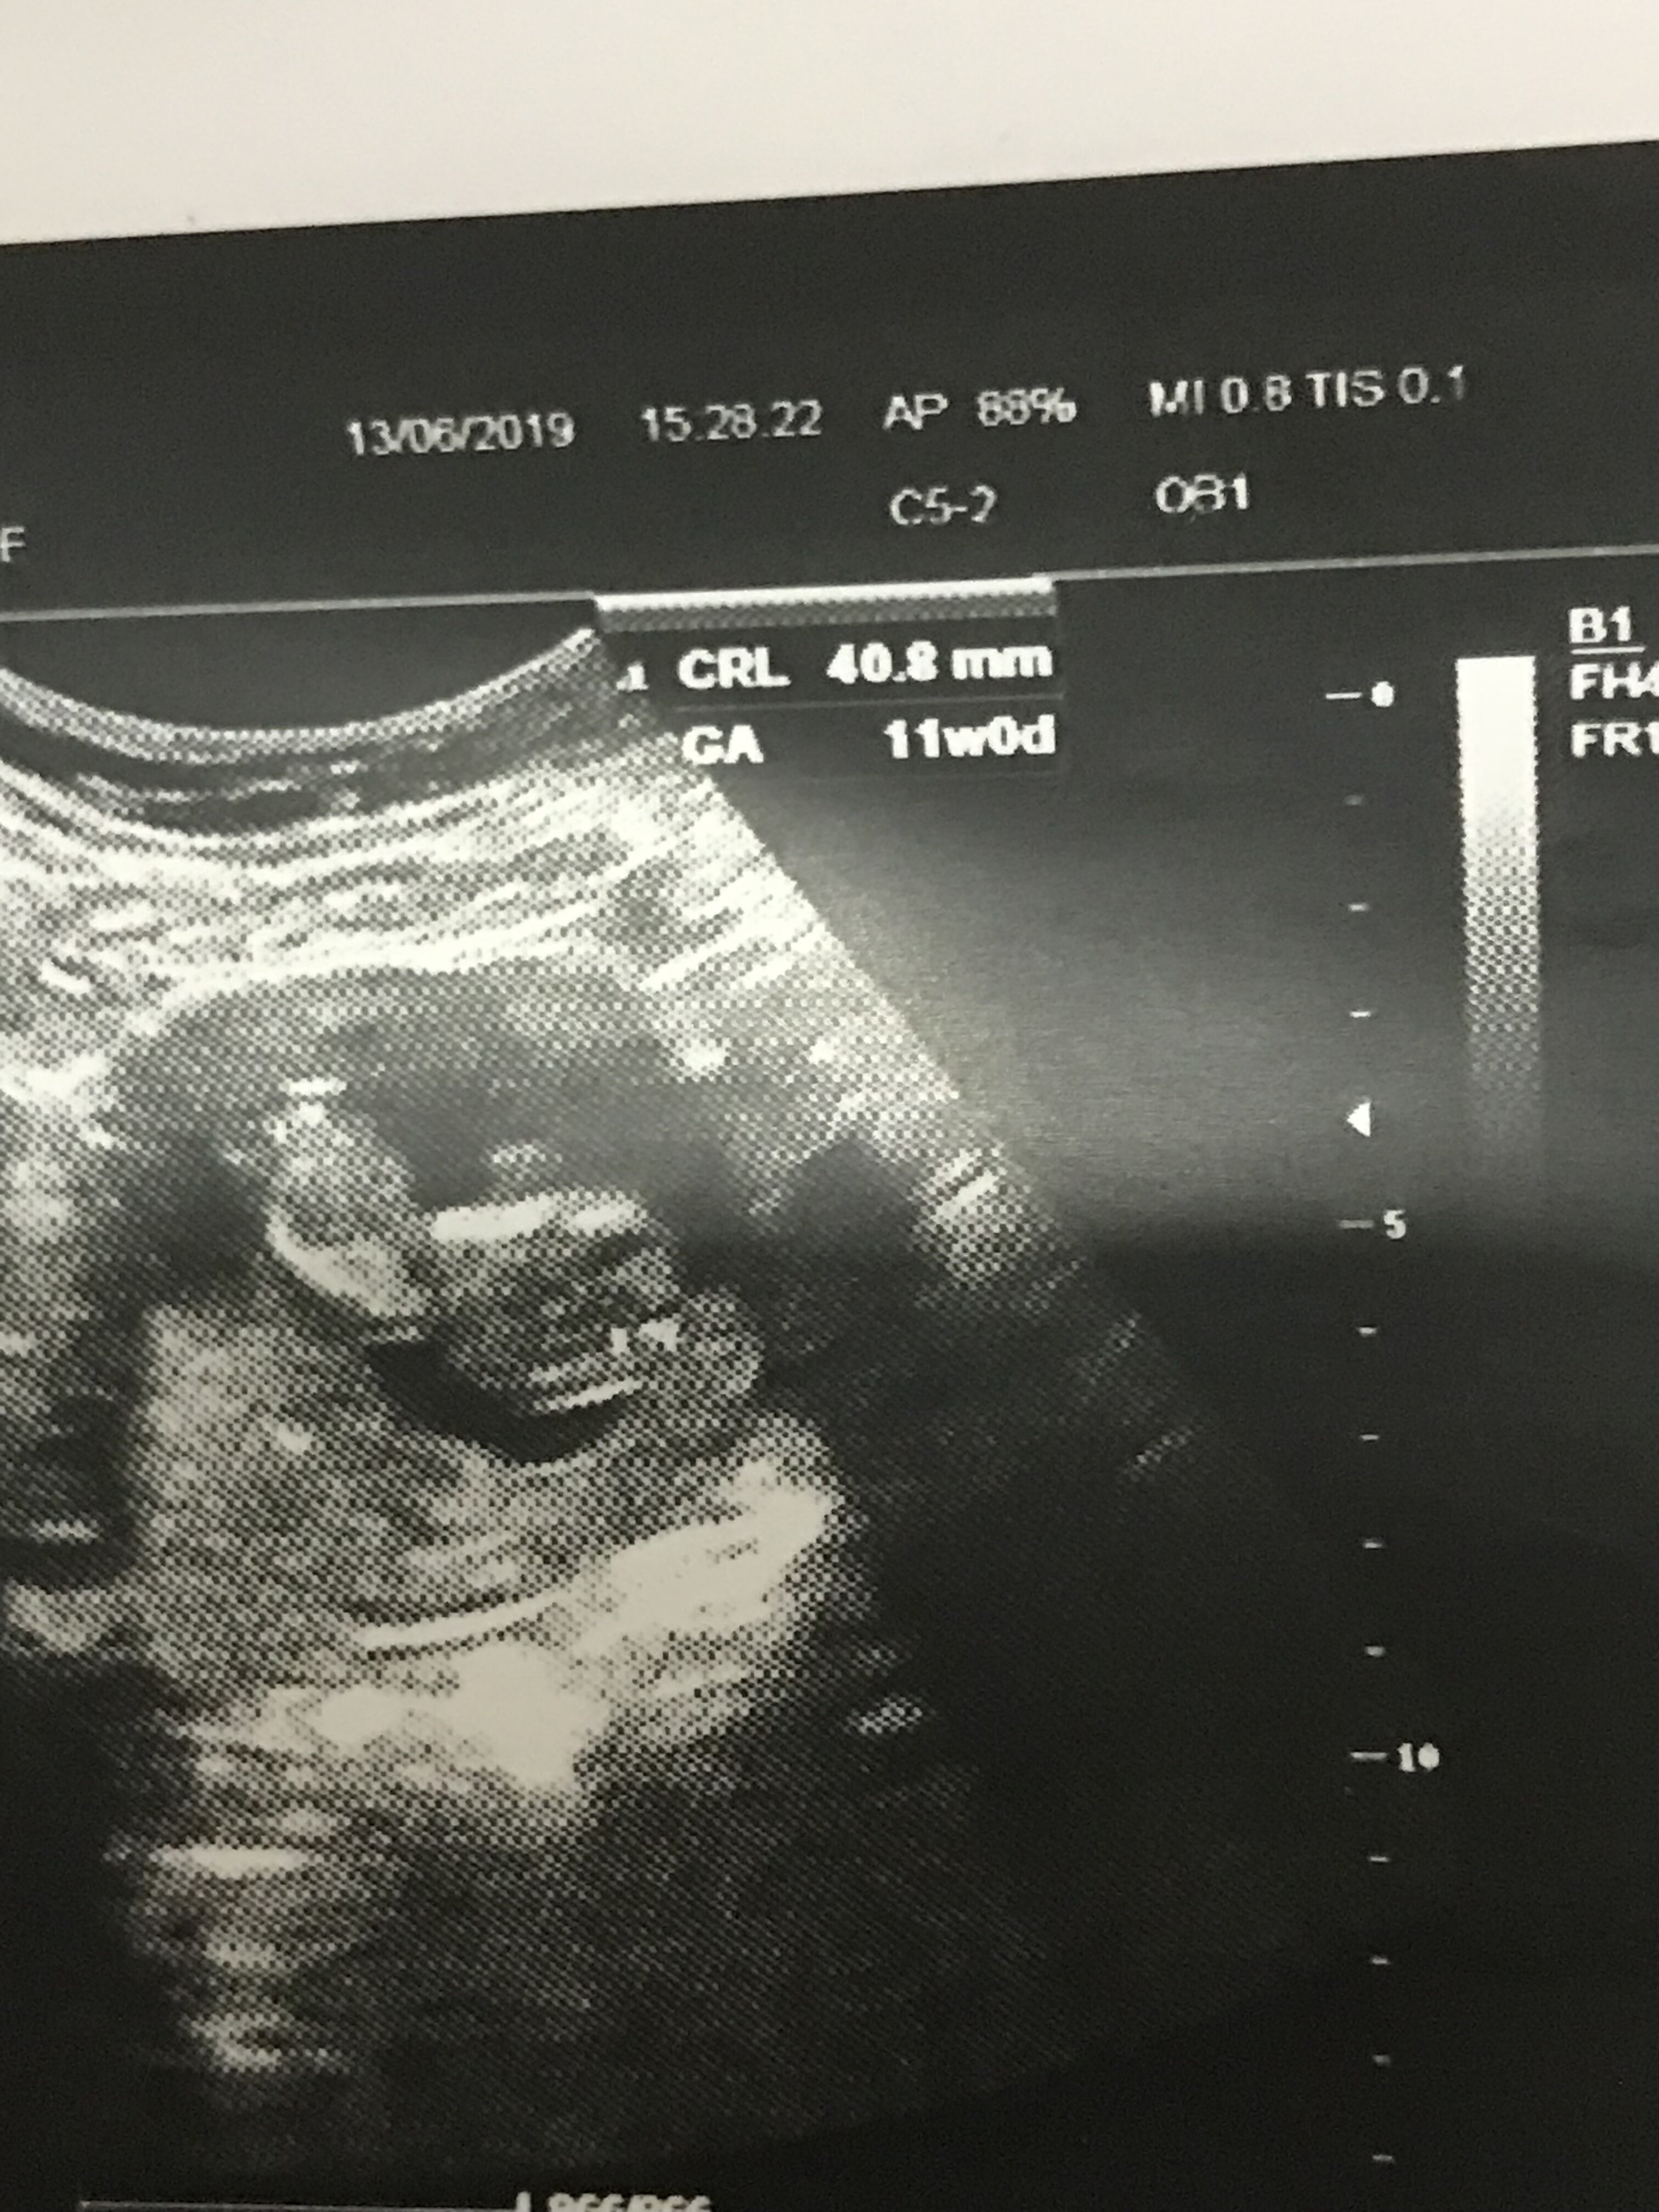

Ultrason sonucuna göre cinsiyet tahmini

Merhabalar gönderdiğim usg ye göre cinsiyet yorum yapar mısısnız

Selamlar malesef gönderdiğiniz resim sonuca ulaşmamız için yeteterli veri içermiyor. Lütfen aşağıdaki konumuzu inceleyerek ona göre resim atabilir misiniz ?